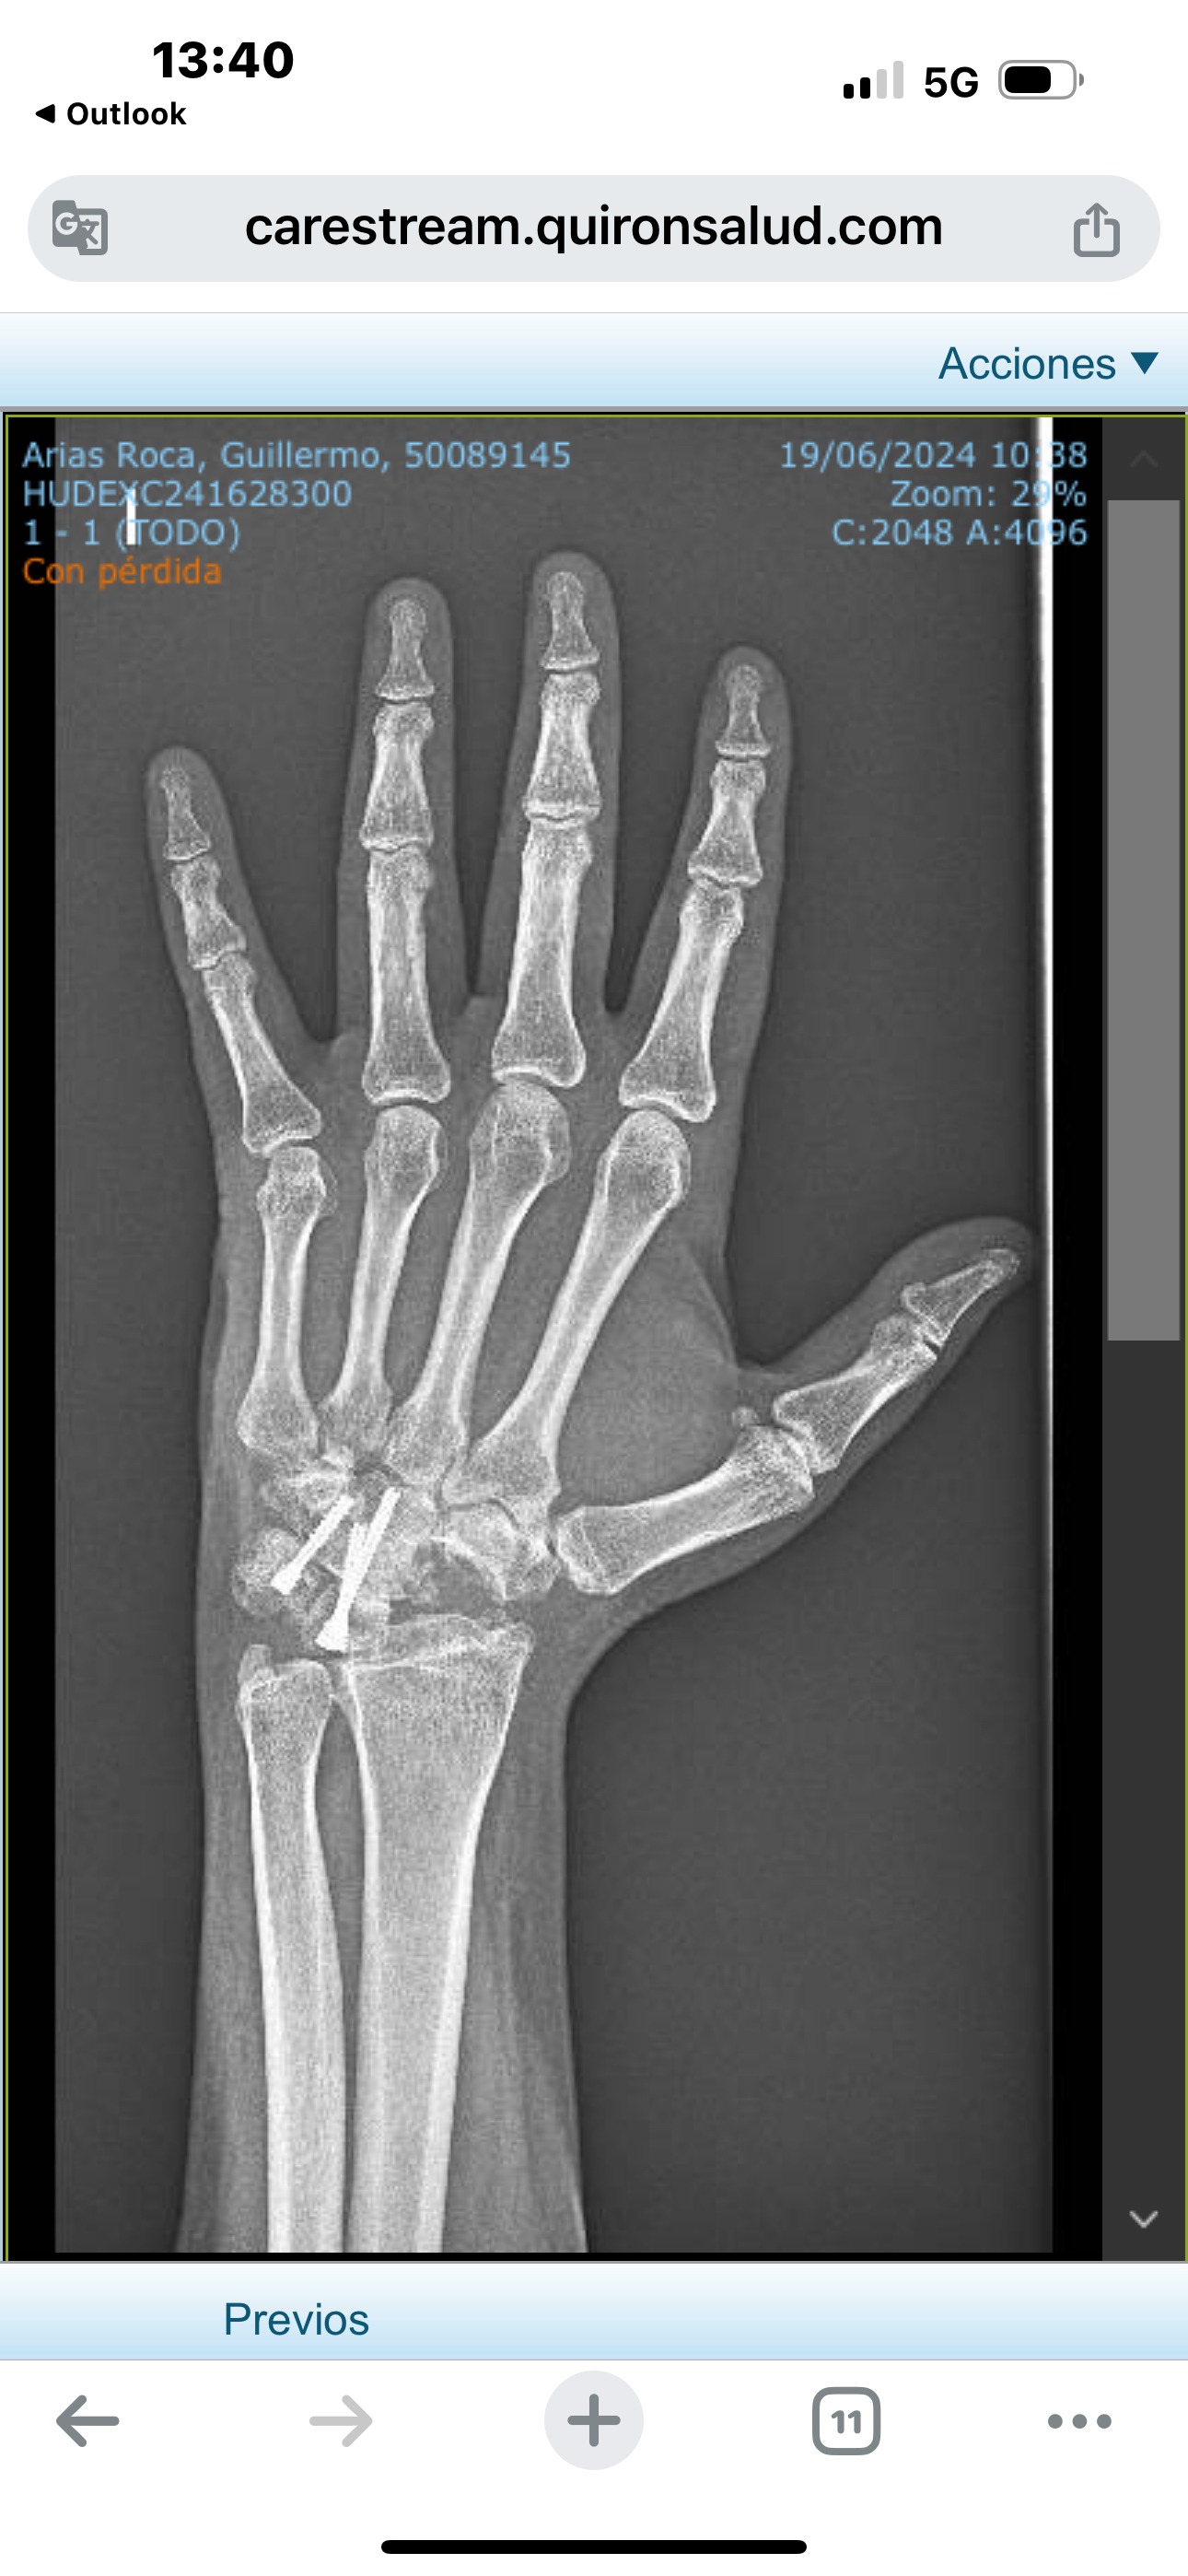

El 19 de octubre de 1992, con 19 años recién cumplidos, sufrí un grave accidente laboral en la fábrica Pinturas Lepanto de Binéfar al caer desde una carretilla elevadora. Las lesiones fueron múltiples: fracturas en la mano, el codo, la espalda y un traumatismo craneoencefálico que me dejó inconsciente durante horas. Desde entonces, he vivido con un dolor constante (EVA 10).

En 1998 presenté otra demanda, pero mi abogado no se presentó al juicio. En 2008 ingresé en la Unidad del Dolor con diagnóstico de Síndrome Regional Complejo. Seis cirugías, un neuroestimulador y años de medicación no aliviaron el sufrimiento.

En marzo de 2024, decidido a terminar con mi vida, un amigo me convenció de ver a un especialista. Ahí descubrieron que llevaba 31 años con la muñeca rota: una simple operación resolvía gran parte del problema. La pregunta es inevitable: ¿cómo nadie lo vio antes? ¿Cómo se permitió tanto encubrimiento, soborno y abandono?